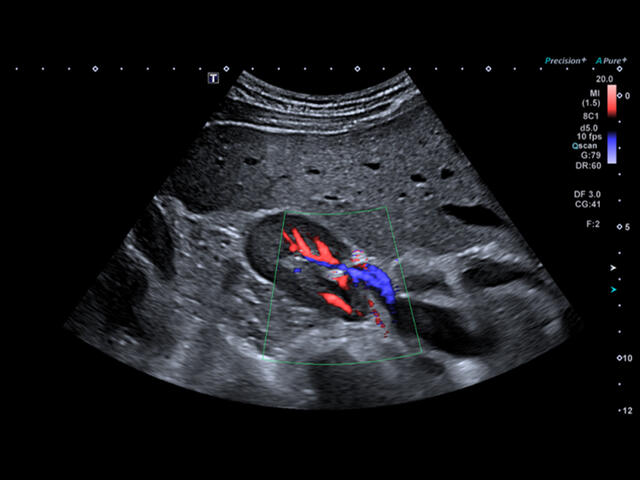

- SMI. Опция, упрощающая визуализацию микроциркуляторного русла. С ее помощью обследуются сосуды с низкой интенсивностью кровотока, изучаются наиболее тонкие структуры. SMI упрощает диагностику новообразований, минимизирует вероятность ошибки.

Уровень сосудистой визуализации SMI в сочетании с высокой частотой кадров повышает диагностическую достоверность при оценке поражений, кист и опухолей.

SMI с цветовой кодировкой позволяет одновременно отображать информацию о потоках и оттенках серого с высокой временной и пространственной информацией.